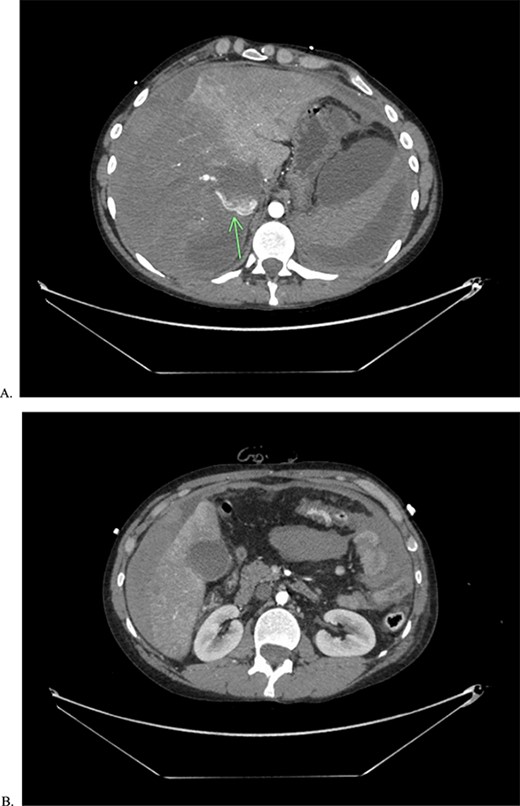

A 21-year-old male presents to the emergency department (ED) with acute onset abdominal pain. The patient has a clinical history suggestive of EDS including aortic insufficiency, joint instability, spontaneous pneumothorax, acquired foot deformity, and iliofemoral deep vein thrombosis and has been undergoing work up for EDS. Initial CT of the abdomen and pelvis (Fig. 1) revealed pneumoperitoneum and free fluid suggestive of a perforated hollow viscus without any visceral aneurysms. Therefore, the patient was taken to the operating room (OR) emergently.

CT of abdomen and pelvis in both abdominal (A) and lung (B) window to show pneumoperitoenum as well a thickened loops of bowel.